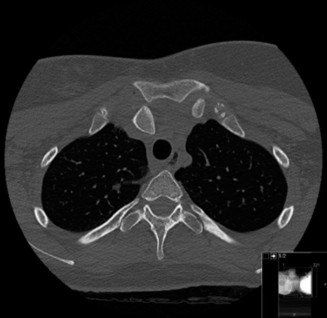

While the clinical examination provides a robust working diagnosis, advanced imaging is paramount for surgical templating, prognosticating, and definitively ruling out concomitant intra-articular or osseous pathology. The initial imaging modality must always be a high-quality, orthogonal radiographic series of the shoulder, including a true anteroposterior (Grashey) view, a scapular Y view, and an axillary lateral view. In a 76-year-old with a partial-thickness rotator cuff tear, radiographs may appear surprisingly benign.

However, subtle radiographic clues often hint at the underlying pathology. The Grashey view is scrutinized for the acromiohumeral interval (AHI). A normal AHI is between 7 and 14 mm. An AHI of less than 7 mm is highly indicative of a massive, chronic full-thickness rotator cuff tear allowing superior migration of the humeral head due to the unopposed upward pull of the deltoid. In our patient with a partial tear, the AHI will likely be preserved, as the intact portion of the cuff continues to depress the humeral head. We also evaluate the greater tuberosity for sclerosis, cortical irregularity, or cystic changes—the so-called "footprint cysts" that develop secondary to chronic micro-avulsions and hypervascularity at the tendon insertion.

The scapular Y view and supraspinatus outlet view are essential for evaluating acromial morphology. Bigliani classified acromial shapes into three types: Type I (flat), Type II (curved), and Type III (hooked). A Type III hooked acromion significantly decreases the subacromial volume and is highly correlated with an increased incidence of rotator cuff tears, acting as a relentless mechanical abrading force against the bursal surface of the supraspinatus tendon. Additionally, the axillary view helps assess for glenohumeral osteoarthritis and ensures the humeral head is concentrically reduced, ruling out chronic subtle dislocations.